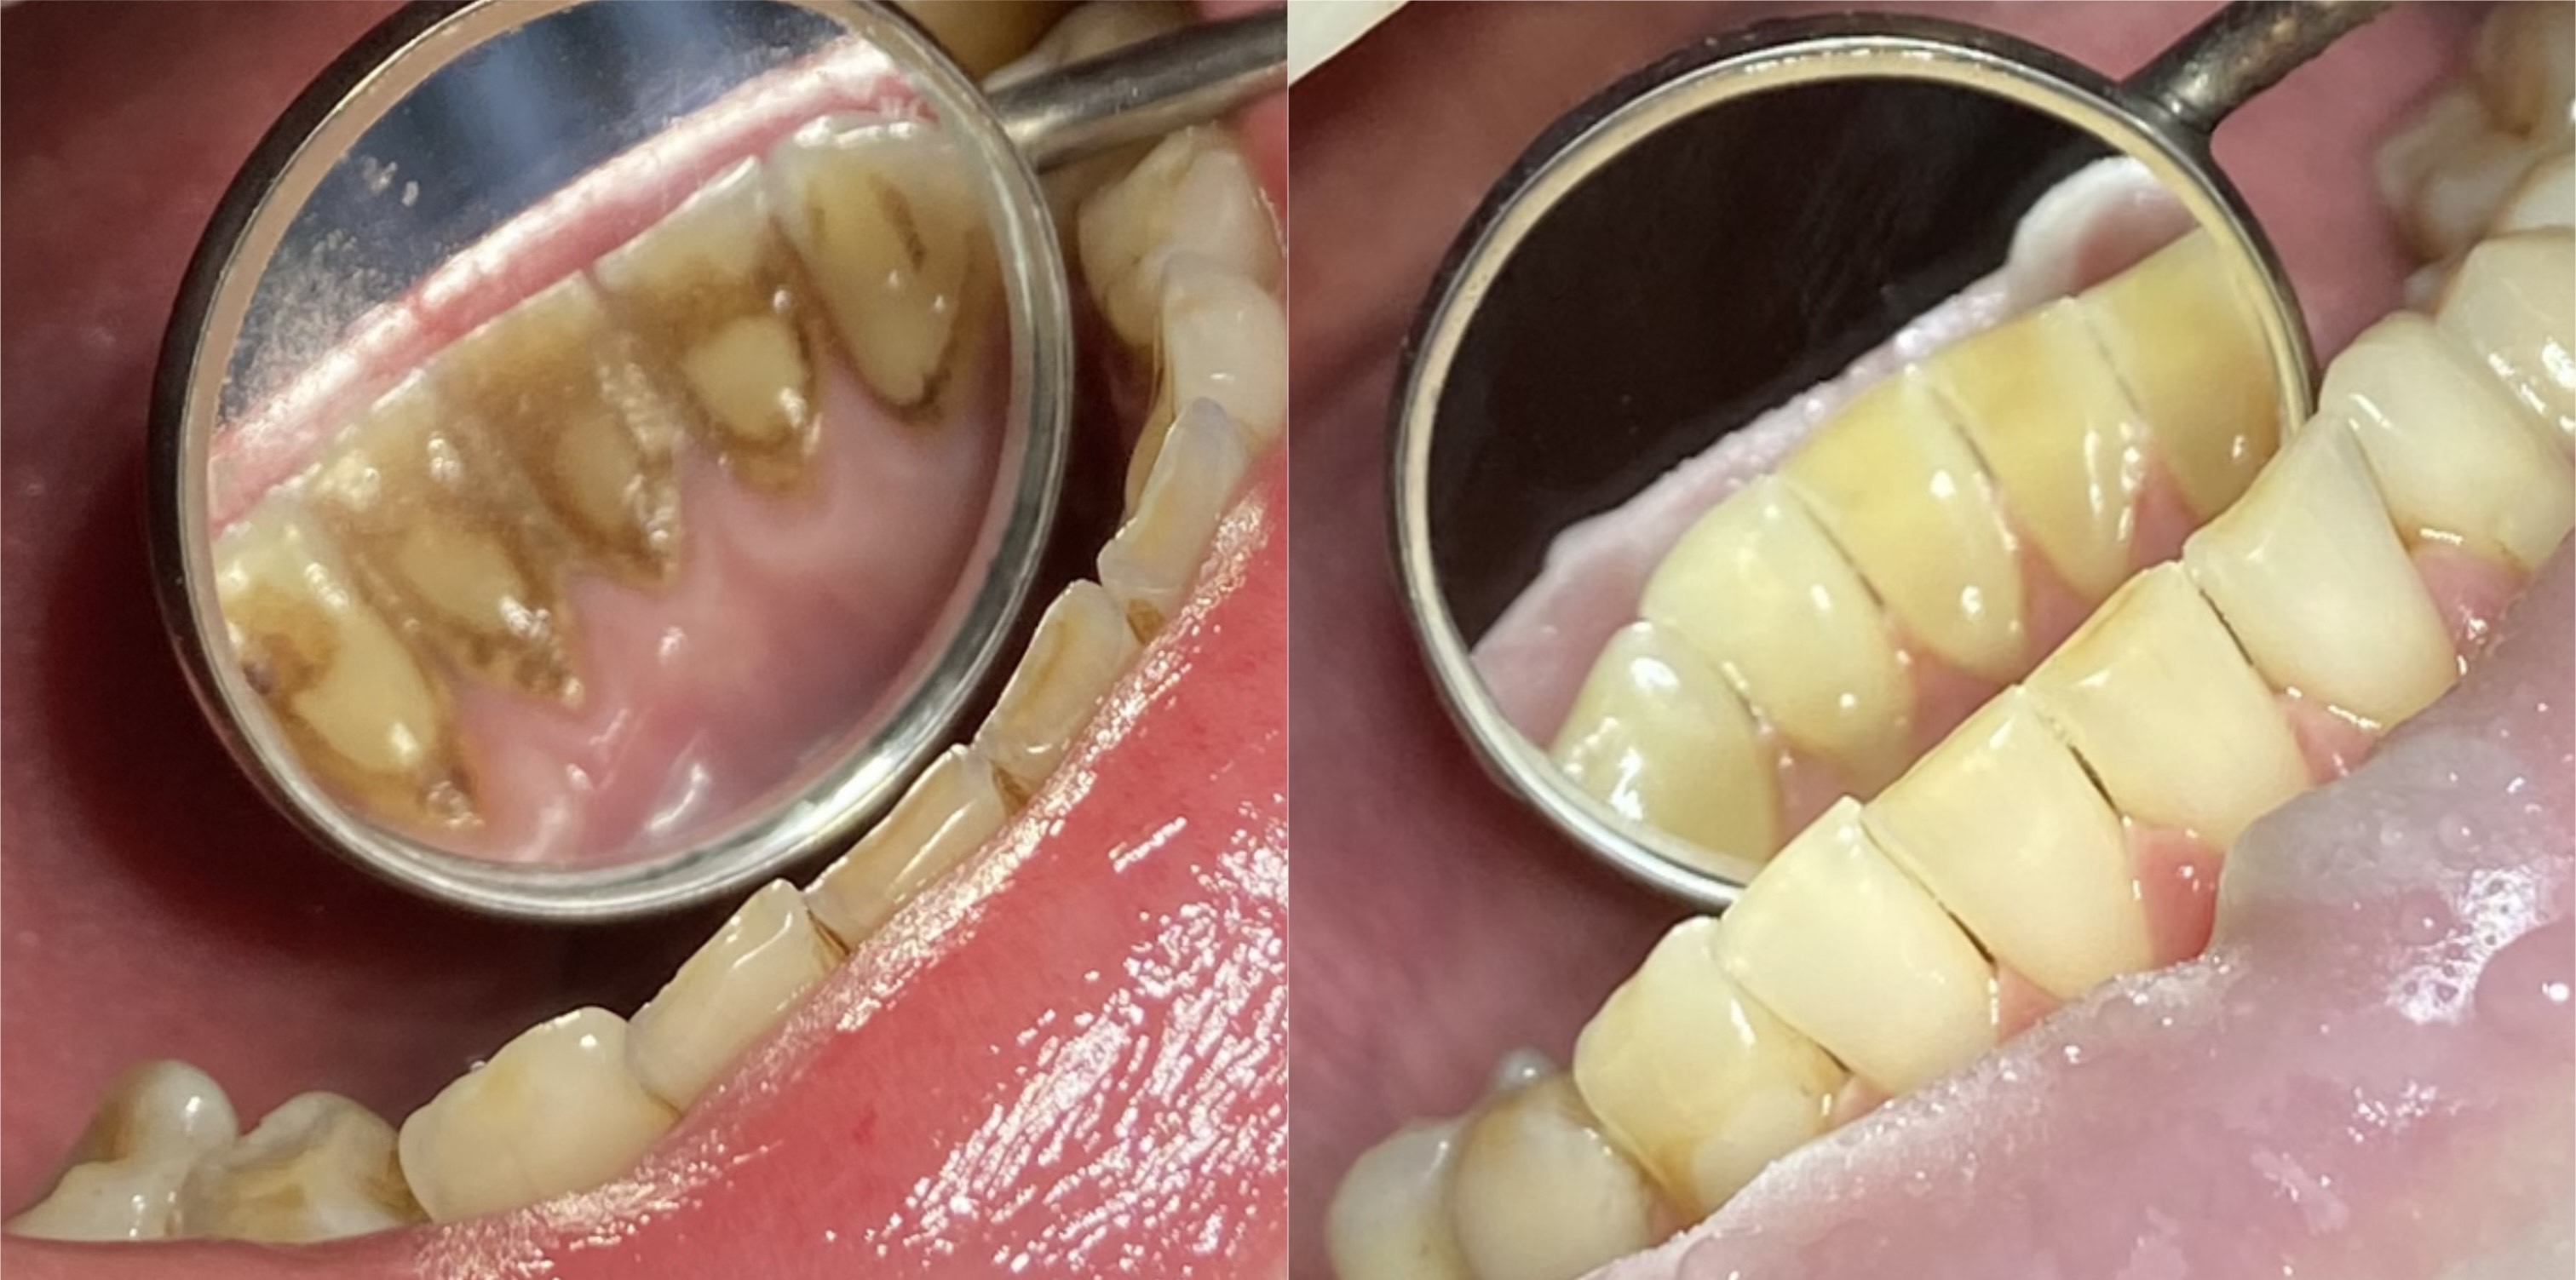

Профессиональная гигиена с использованием ультразвука включает в себя: - удаление твердых зубных отложений с помощью ультразвукового скейлера - полировка зубов профессиональной щеткой и пастой "Kerr super polish" - покрытие зубов фторосодержащим препаратом - метод рекомендован для удаления зубного камня |

Профессиональная гигиена с использованием технологии AirFlow включает в себя: - снятие пигментированного налета с применением порошкового метода AirFlow, при котором из специальногохэнди - бластера под давлением подается профессиональный мелкодисперсный порошок - полировка зубов профессиональной щеткой и пастой - покрытие зубов фторосодержащим препаратом - Использование технологии Air Flow позволяет удалить налет от чая, кофе, так называемый "налет курильщика". С твердыми зубными отложениями (зубной камень) AirFlow не справится |

Полный комплекс профессиональной гигиены полости рта включает в себя:

- удаление зубного камня ультразвуком

- удаление пигментированного налета с помощью AirFlow

- полировка зубов профессиональной щеткой и пастой "Kerr super polish"

- покрытие зубов фторосодержащим препаратом